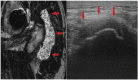

Background: Metal artifact reduction sequence magnetic resonance imaging (MRI) scan is a common method to detect adverse reaction to metal debris in total hip arthroplasty (THA). It might be quicker and cheaper if ultrasonography (US) could screen for the need for an MRI. However, both require trained personnel.

Material and methods: We examined 205 patients with hip resurfacing arthroplasty, metal-on-metal or metal-on-polyethylene THA with both MRI and US. US was performed by an orthopedic surgery resident who was trained according to a standardized training program in musculoskeletal US. Results from MRI were used as gold standard.

Results: US had a sensitivity of 0.92 (95% CI 0.81-0.98) and specificity of 0.94 (95% CI 0.89-0.97) for detecting PT. It had a positive predictive value of 0.84 (95% CI 0.73-0.91) and a negative predictive value of 0.97 (95% CI 0.93-0.99). US performed similarly in obese and non-obese patients.

Conclusions: US had a high sensitivity and specificity for detecting PT when performed by an orthopedic surgery resident. Trained orthopedic surgeons could screen for the need of an MRI scan when searching PTs.